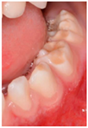

IMAGE 1![]() | Caries | 69 (19.2) |

| Enamel defect | 249 (69.4) | |

| No dental lesions | 15 (4.2) | |

| I do not know | 26 (7.2) | |